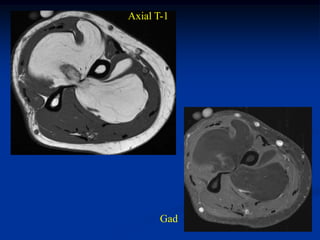

Case #1196.2 Ossifying Lipoma Cor T-1 Axial T-2 53 yr male with painless mass in knee for 3 yrs